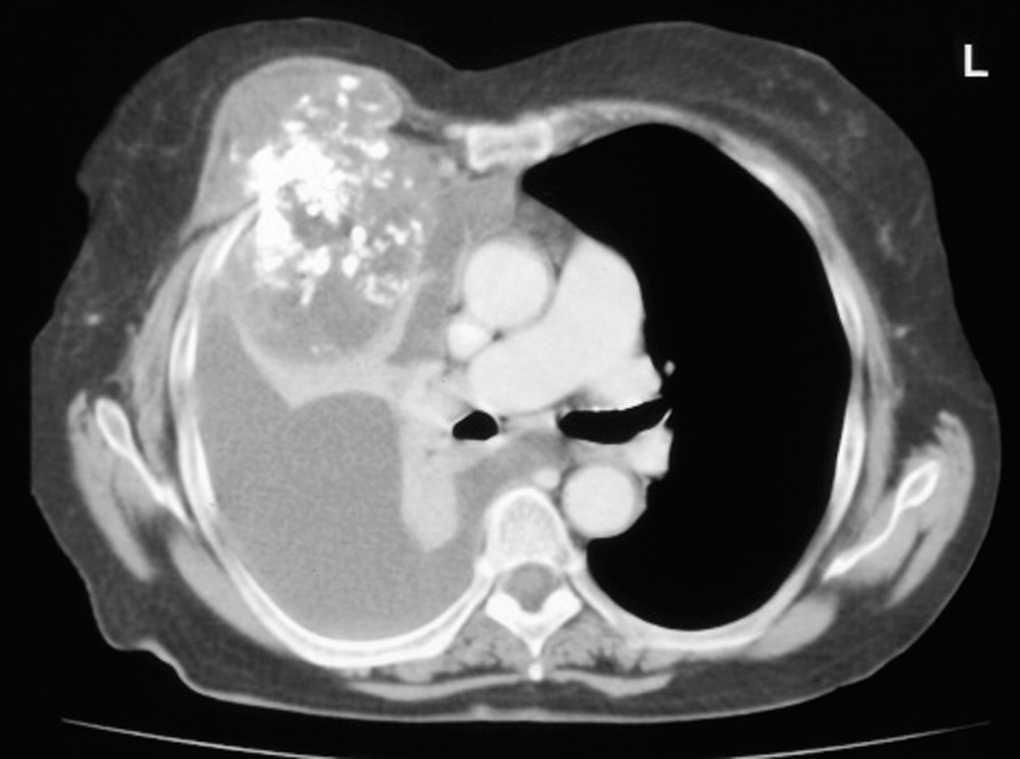

Mujer de 79 años que viene sufriendo disnea de un mes de evolución junto con una masa dolorosa en la pared torácica derecha, que ha ido incrementado progresivamente en tamaño y dolor en los últimos meses. La exploración física demuestra una abolición del murmullo vesicular derecho. En la radiografía de tórax y en la tomografía computarizada torácica se pone de manifiesto un gran tumor de aproximadamente 10 cm x 9 cm x 10 cm, que se originaba en la 4.a o 5.a costillas derechas y destruía la pared torácica. En el interior del tumor se aprecian abundantes calcificaciones y un derrame pleural derecho que genera atelectasia compresiva del pulmón de ese lado (fig. 1). El líquido pleural analizado no demostró la presencia de células malignas. Los valores espirométricos demostraron una insuficiencia ventilatoria de tipo restrictiva (FEV1: 850 ml; FVC: 1.110 ml). Se intervino a la paciente y se realizó una resección completa del tumor, con un margen de seguridad oncológica de 5 cm alrededor de éste, por lo que requirió de una prótesis de Goretex® para cubrir el defecto generado. El estudio anatomopatológico confirmó que se trataba de un condrosarcoma de grado III, que se originaba en la 4.a costilla derecha y que no invadía los bordes de resección costal (fig. 2). Las revisiones posteriores a lo largo de 1 año demostraron una recuperación completa de los valores espirométricos (FEV1: 1.460 ml; FVC: 1.990 ml), así como la desaparición del dolor y de la masa de pared torácica.

Fig. 1.